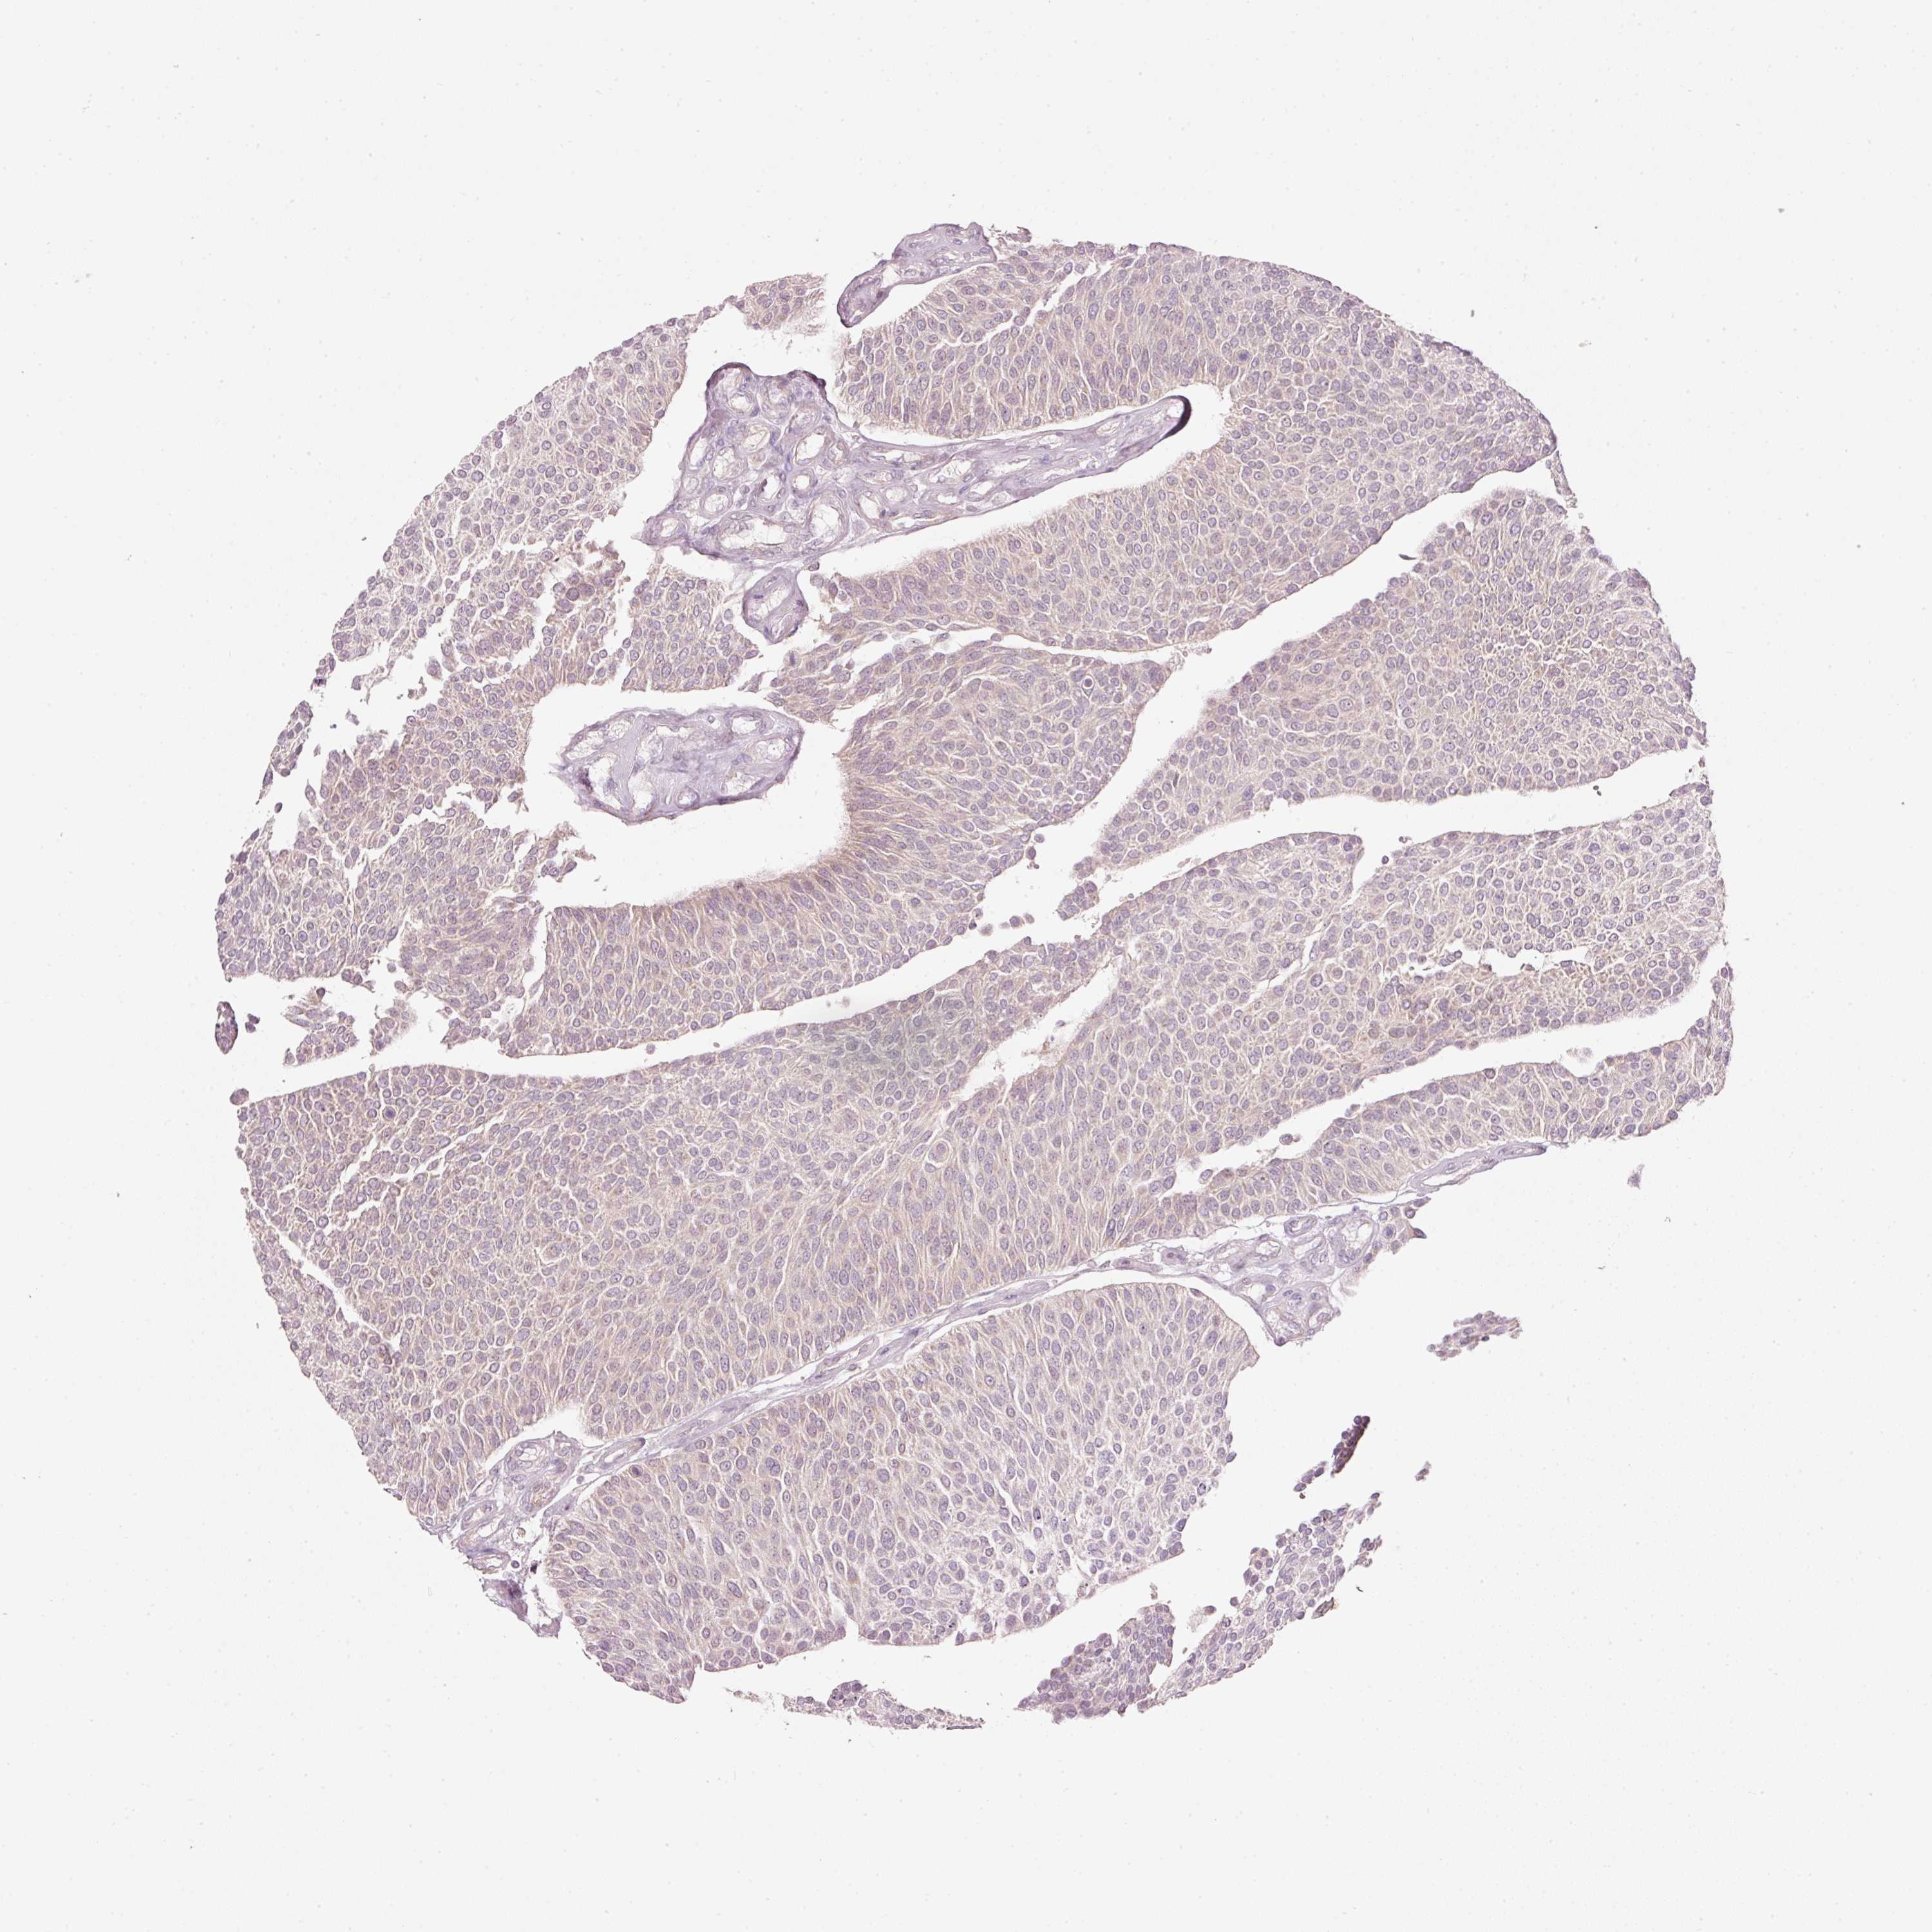

UROTHELIAL CANCER - Protein expressioni

A mouse-over function shows sample information and annotation data. Click on an image to view it in a full screen mode. Samples can be filtered based on level of antibody staining by selecting one or several of the following categories: high, medium, low and not detected. The assay and annotation is described here.

Note that samples used for immunohistochemistry by the Human Protein Atlas do not correspond to samples in the TCGA dataset.

Antibody stainingi

Antibody staining in the annotated cell types in the current human tissue is reported as not detected, low, medium, or high, based on conventional immunohistochemistry profiling in selected tissues. This score is based on the combination of the staining intensity and fraction of stained cells.

Each image is clickable and will lead to virtual microscopy that enables deeper exploration of all samples and also displays staining intensity scores, fraction scores and subcellular localization as well as patient and tissue information for each sample.

Antibody HPA053900

Staining

High

Medium

Low

Not detected

Intensity

Strong

Moderate

Weak

Negative

Quantity

>75%

75%-25%

<25%

None

Location

Nuclear

Cytoplasmic/membranous

Cytoplasmic/membranous,nuclear

Urothelial carcinoma, High grade

Urothelial carcinoma, NOS

Urothelial carcinoma, Low grade